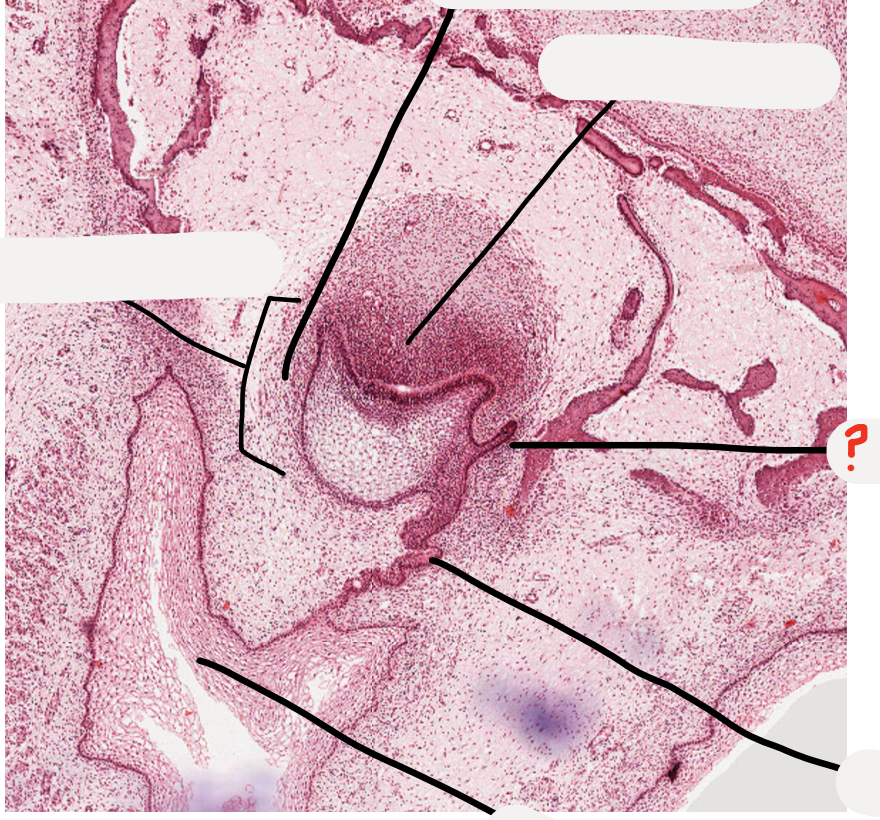

1

Q

what stage is this tooth germ?

A

cap stage